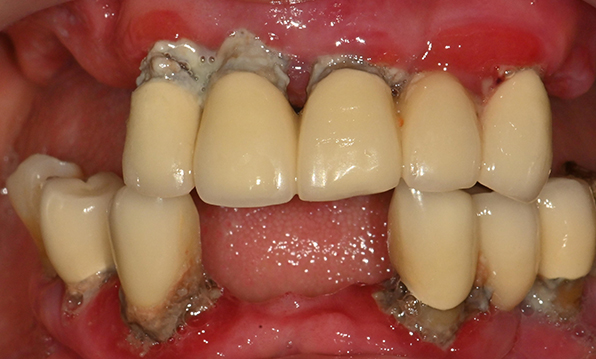

치아가 하나도 남아있지 않거나 전체적으로 상실된 경우 추천합니다.

전체 임플란트가 필요한 경우

치아가 얼마 남아있지 않은 경우

치주질환이 심해, 치아가 있더라도 제 기능을 하지 못하는 경우

틀니 사용이 불편한 경우

전체 임플란트를 해야하는 환자들은

대부분 고령의 환자들로 오랜 틀니 사용

또는 노화로 인해 치조골이

거의 남아있지 않는 경우가 많습니다.

이 때, 치조골 이식을 병행하여 잇몸뼈 재건 후 안정적인 임플란트 식립을 하고 있습니다.